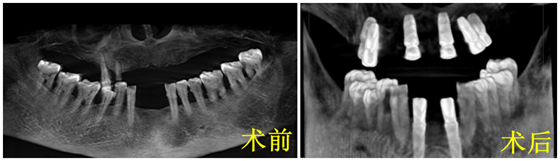

11月7日,湘雅常德医院口腔科主治医师向峰再次助力汉寿县洲口镇中心卫生院成功为一位82岁高龄的老年女性患者下颌植入3枚种植体,这也是该卫生院及乡镇实施的最大年龄的种植患者。 &...

医院里每天都在上演着无数暖心故事,那些炽热的感动瞬间就在身边,他们未必光芒万丈,但始终温暖有光……近日,在湘雅常德医院口腔科,医护人员用心用爱为一名“特殊”人士成功种牙...